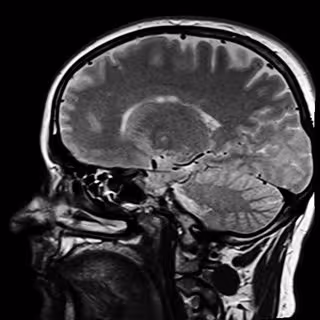

Modelos matemáticos contra tumores cerebrales

Cerebro

El grupo de investigación de Oncología Matemática de la Universidad de Castilla-La Mancha (UCLM) liderará un proyecto internacional de investigación sobre el uso de modelos matemáticos que permitan el diseño de terapias personalizadas en pacientes diagnosticados de glioblastoma, el tumor cerebral primario más frecuente y más agresivo que existe.

El glioblastoma es el tumor más común y más maligno del sistema nervioso central, con una incidencia de 6 casos por cada 100.000 habitantes al año y con una supervivencia de promedio de tan solo 15 meses desde su diagnóstico y una calidad de vida de quien lo sufre muy mala, ha informado la UCLM en nota de prensa.